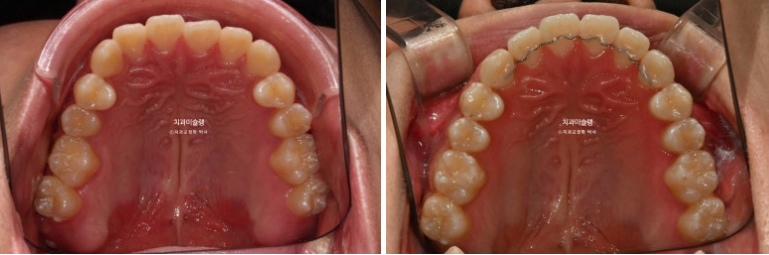

중심선이 어긋나있고 앞니 개방교합이 보입니다.

주걱턱으로 인해 앞니가 거꾸로 물리는 반대교합이 있습니다.

치료계획은 아래 사랑니 2개를 발치하고 사랑니 공간으로 치열을 뒤로 미는 것 입니다.

중심선은 정확히 맞으며 개방교합은 충분히 해소되었습니다.

반대교합은 개선되었고 교합관계는 1급을 달성

아래 어금니들은 가용한 사랑니 공간을 최대한 이용하며 뒤로 들어갔습니다.